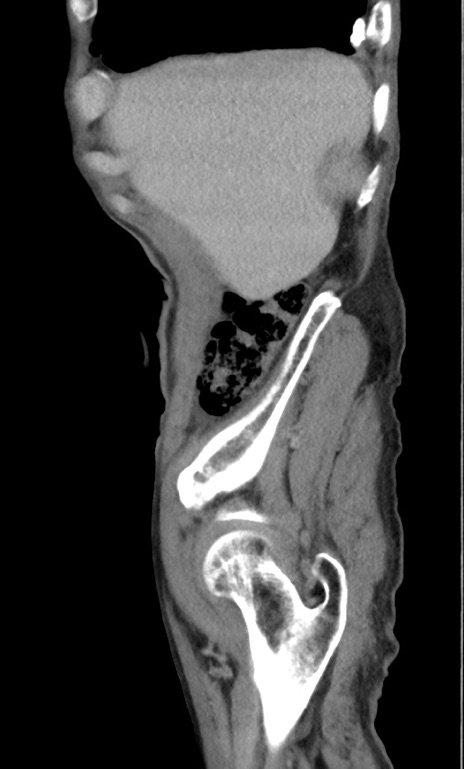

症例3(矢状断像)

【症例】 70歳代男性

【主訴】右鼠径部腫瘤、疼痛

【現病歴】本日朝より上記主訴あり、受診。

【既往歴】膀胱癌にて膀胱全摘、両側尿管皮膚瘻

【データ】WBC 5600、CRP 0.56